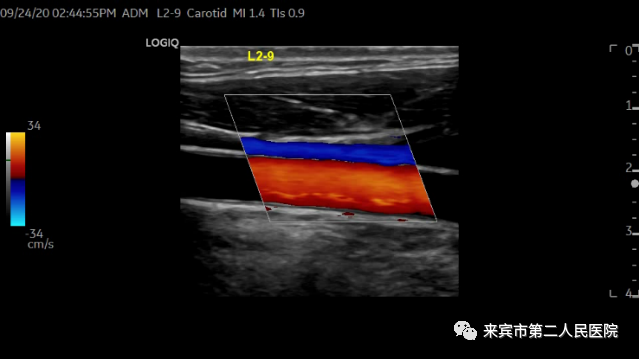

二、彩超在血管检查中的应用:

彩超可以对人体的颅内外动静脉,心血管以及四肢动静脉进行检查,应用彩色多普勒可以检测到颅内血管内血流速度,以此判断有无血管痉挛或者是血管狭窄。

通过对颈部血管的检测,可以清晰地显示出颈部动脉壁是否增厚、斑块、血栓、狭窄、闭塞等等,而通过对四肢血管检测,可以检查出动脉有无狭窄、闭塞以及血流的速度,可以排除四肢静脉有无血栓形成,以及有无瓣膜功能不全、反流等等情况。

2.从多个维度观察血管、组织的血流灌注,明确诊断,CDFI彩色及PDI能量多普勒。